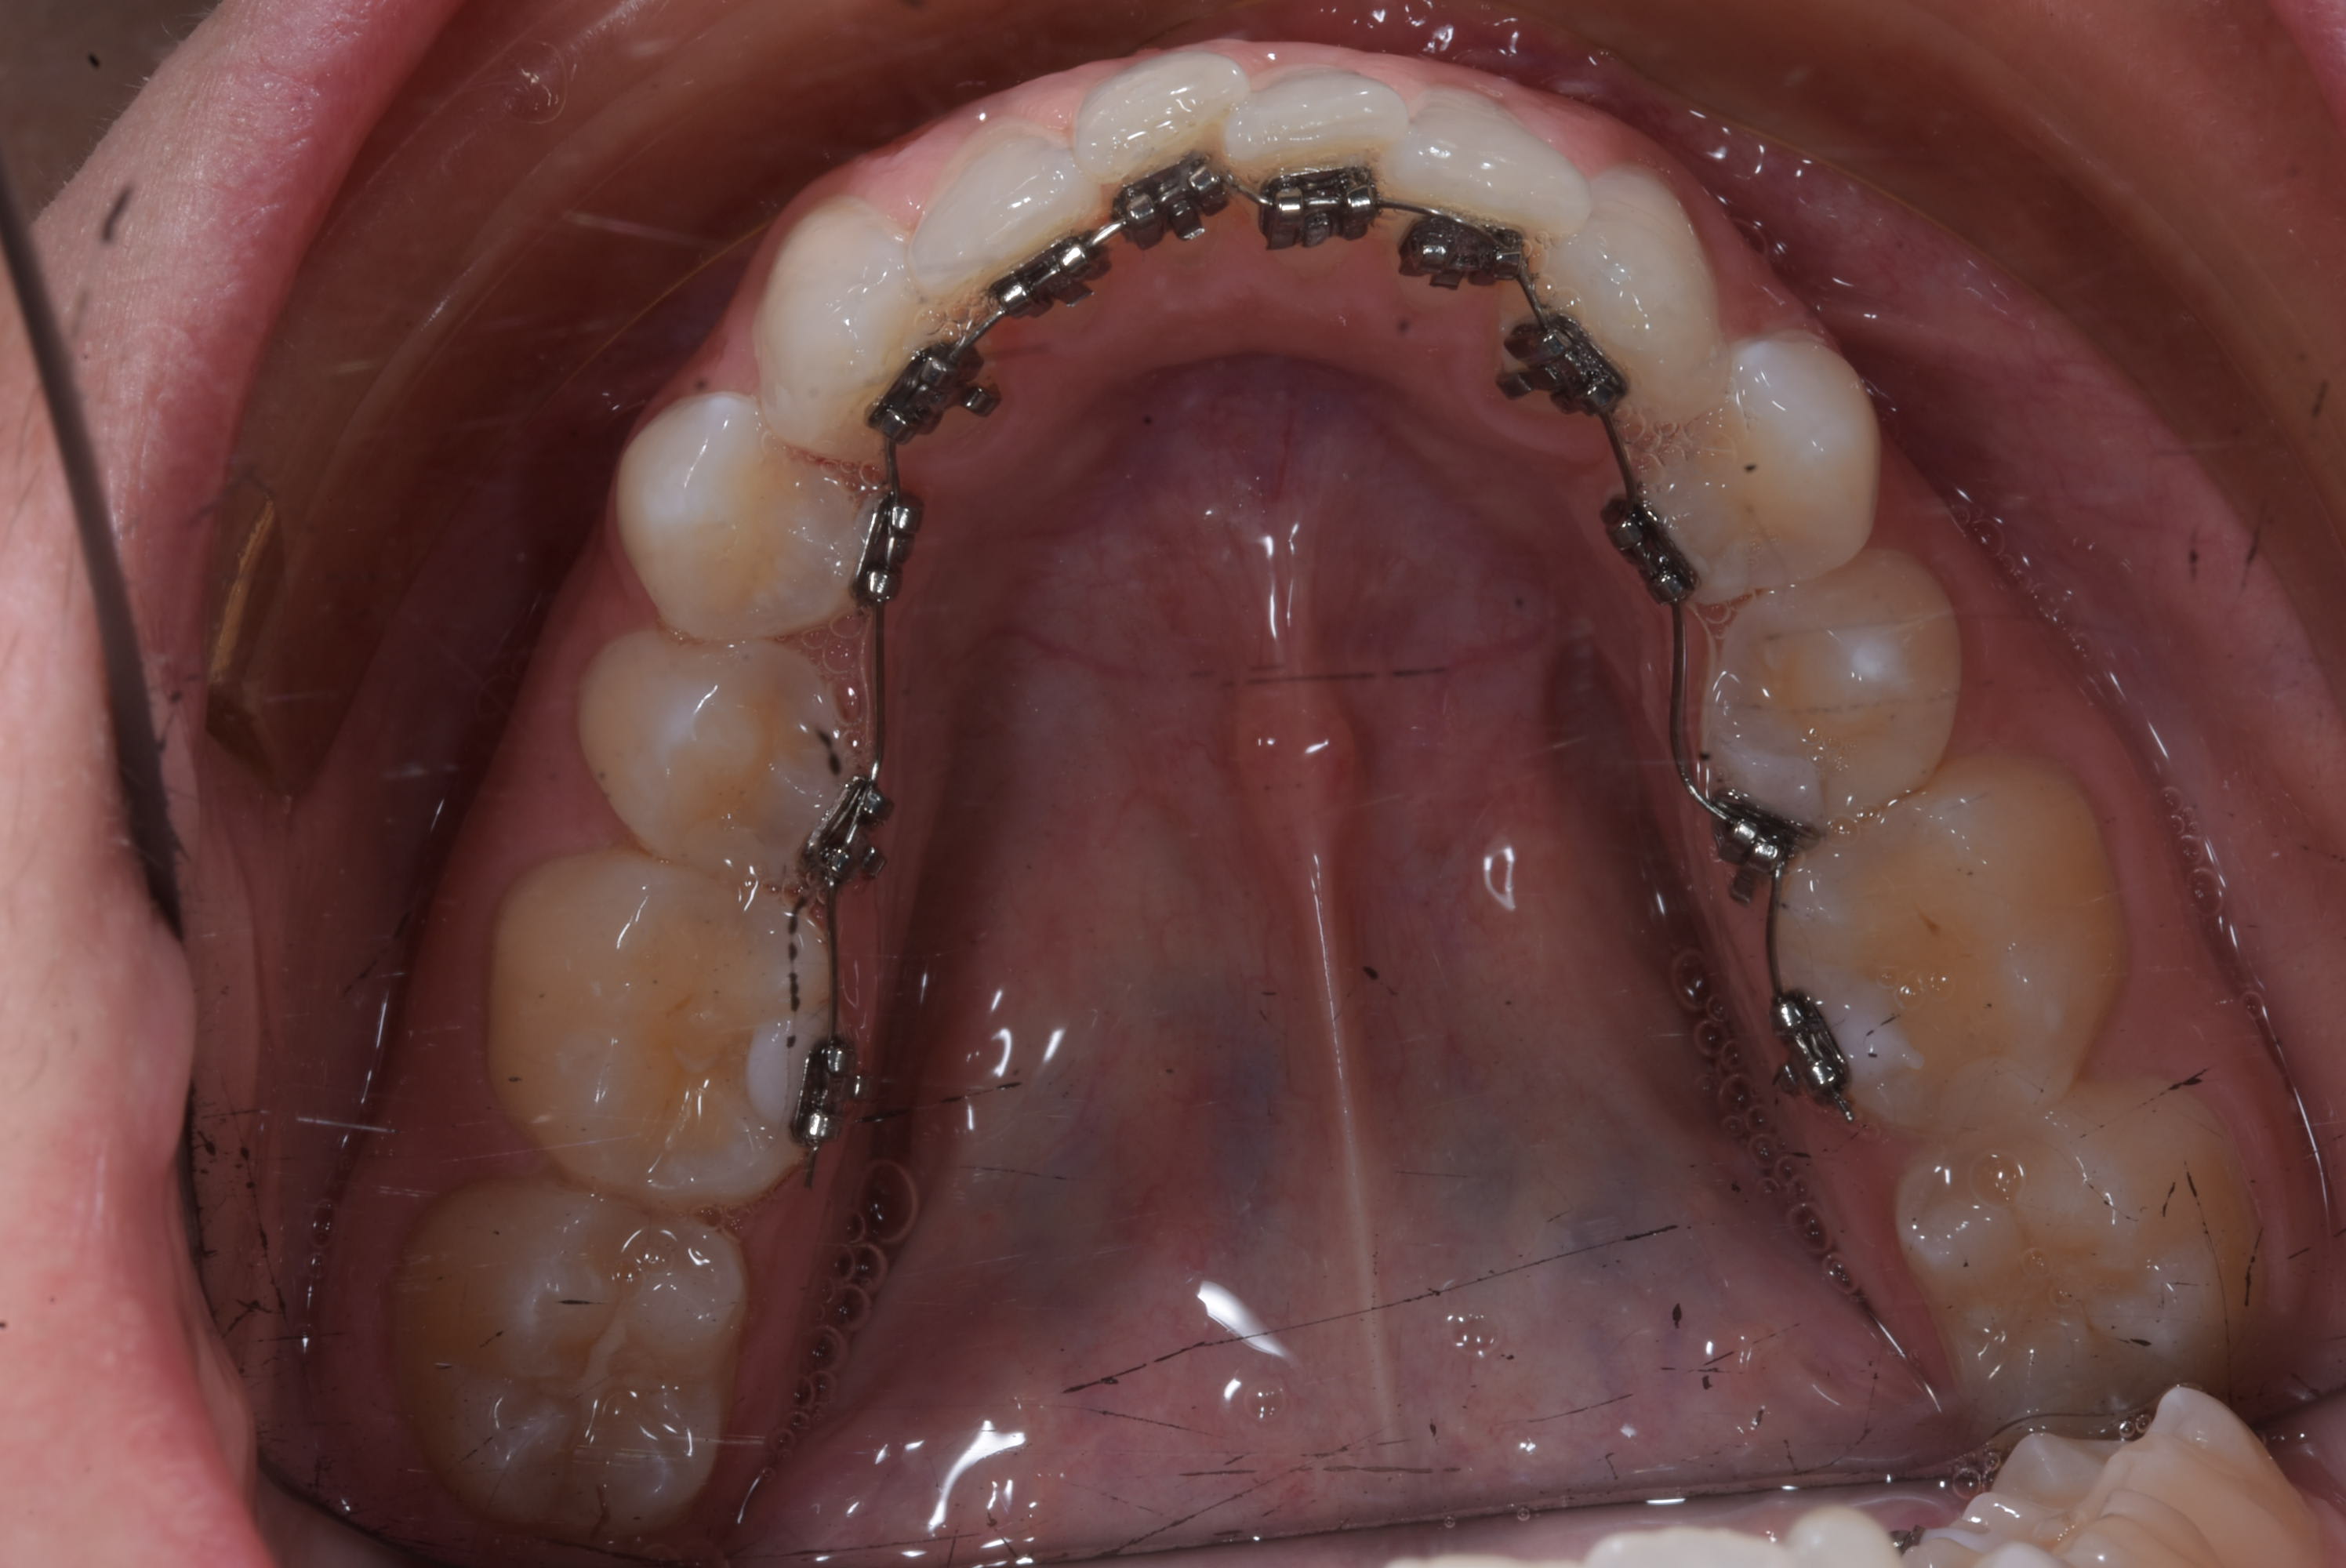

Si joint une photo d'une patient Japonaise traité par un dentiste Japonais sur PP, venue me voir en consulte suite à la fermeture du Cabinet.

Le type de bracket utilisé ici sont équivalent à ceux de RMO mais sans les doubles ( enfin triple slote ) .

Dans les deux cas la partie principal est un tube ce qui limite vos possibilité d'action. Pour vous rendre compte des limitation essayé de voir comment vous traiteriez un cas vestibulaire avec de telle bracket ?

- zero prescription dont toute l'information doit être transmise par pliage de fil. Seul soucie faire passer un fil avec pliage dans un tube ça peut poser soucie. C'est la raison pour laquelle l'on équipe habituellement seul la dent terminal avec un tube.

- Très compliqué d'utiliser des auxillaires.

En lingual vous rajouter le fait qu'un arc doit avoir des pliures assez importante. Déjà entre les PM et les Molaire il y a un pas. Vous faite comment pour enfiler un fil avec des angles de 6 à 6 , sachant que vous avez moins d'espaces entre les bracket ce qui se traduit par une rigidité plus important.